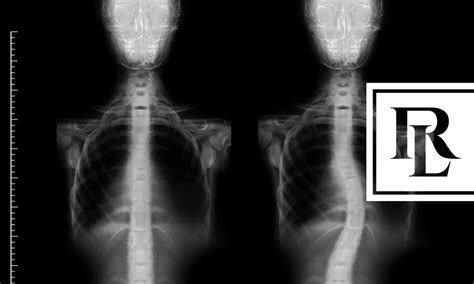

Getting a proper diagnosis is the first step. Doctors typically use X-rays to measure the curve of the spine. From there, the course of treatment depends on the severity of the curve and other factors. Treatment options can include observation (for mild cases), bracing to prevent the curve from getting worse, physical therapy to improve strength and flexibility, and, in severe cases, surgery to correct the curve. Managing scoliosis effectively can make a huge difference in the lives of those affected, helping to ease pain, improve mobility, and maintain a higher quality of life. Regular check-ups are super important to monitor the progression of the curve and adjust treatment as needed. Remember, early intervention and the right kind of care can go a long way in managing scoliosis and its impact.

To be eligible for disability benefits, you typically need to demonstrate that your scoliosis causes significant functional limitations. The SSA assesses your ability to perform basic work-related activities. This includes things like sitting, standing, walking, lifting, and carrying. If your scoliosis makes it difficult or impossible to perform these activities, you might be considered disabled. Medical evidence is crucial for proving your case. This includes X-rays showing the curve of your spine, doctor’s notes, treatment records, and any reports from specialists. The SSA will also consider the impact of your scoliosis on your ability to work, taking into account your age, education, and past work experience. This might sound complicated, but understanding the criteria is the first step in getting the support you need. The SSA’s decision is based on a comprehensive assessment of your medical condition and its effect on your ability to work.

Medical records are the foundation of your claim. Make sure to collect all the relevant documents. This includes X-rays, MRI scans, and any reports from specialists. These records will help to demonstrate the severity of your scoliosis. Doctor’s notes are equally important, as they provide a narrative of your condition, treatment, and progress over time. These notes should include details about your symptoms, physical examinations, and any treatments you have received. If you’ve undergone surgery or other procedures, make sure to include the operative reports and any post-operative notes. Also, include any notes from physical therapy, occupational therapy, or any other rehabilitative services.